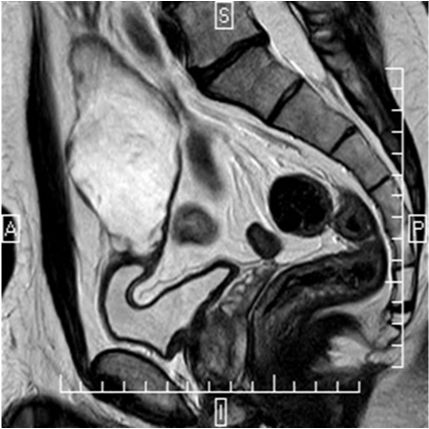

A 42-year-old man presenting a history of 12years of mucinuria. Physical examination revealed no abnormalities. Urinalysis, urine cytology and urine culture were normal. Cystoscopy revealed over the dome of the bladder a nipple shaped lesion covered by mucus. The trans abdominal ultrasonography (US) showed a 10cm cystic mass located above the superior bladder wall. Pelvis magnetic resonance (MR) imaging showed a 11x5, 3x5cm size supravesical midline cyst (Figure 1). No calcifications were observed. The clinical diagnosis was a urachal cyst. The patient underwent a laparoscopic en bloc urachus and bladder dome resection. After a urethral catheterization using 20-F 3 lumen catheters, in 15-30º Trendelenburg position, a longitudinal skin incision above the umbilicus was made to introduce a 12mm Hasson trocar for the camera port. A laparoscopy was performed to rule the presence of peritoneal metastases and the urachal tumor visualization. After both 10mm and 5mm working ports, placed on the left and right umbilicus line were inserted, an additional 5mm assistant port was placed through the left iliac fossa.

Figure 1 T2 sagittal magnetic resonance imaging showing a hyper-enhancement patter mass involving the urachus.

A typical work-up includes cystoscopy with biopsy and radiographic evaluation.2 US, CT, and MR imaging have the ability to display cross-sectional images and therefore are ideally suited for demonstrating urachal anomalies. US may demonstrate a midline fluid-filled cavity with mixed echogenicity and calcifications adjacent to the anterior abdominal wall. A characteristic CT feature of urachal carcinoma is a midline mass anterosuperior to the dome of the bladder with low-attenuation components, which represent pools of mucin at pathologic examination. As with some other mucinous adenocarcinomas of the abdominal organs, urachal carcinomas may produce typical psammomatous calcifications that are well depicted at CT in 50%–70% of cases.7 Magnetic resonance imaging is an excellent staging tool. Because of the presence of mucin within the tumor, increased signal intensity is seen on T2-weighted spin-echo MR images. Both CT and MR imaging are useful for demonstrating intra- and extravesical extension of the tumor.3